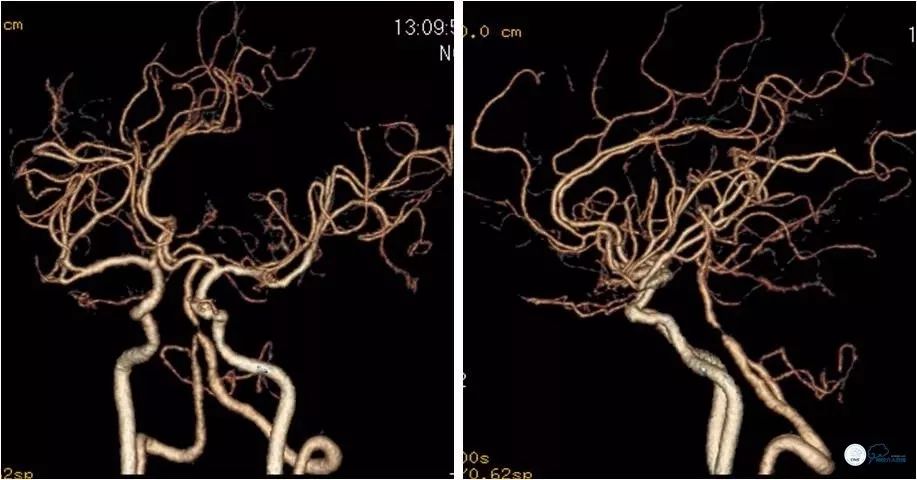

DSA:左椎动脉优势,左椎动脉V1段重度狭窄,右椎动脉V1段中度狭窄,双椎动脉V4-基底动脉下段重度狭窄,狭窄率约为85%,狭窄段有AICA发出,双侧后交通动脉未开放(图6-9)。

图6

图7

图8

图9